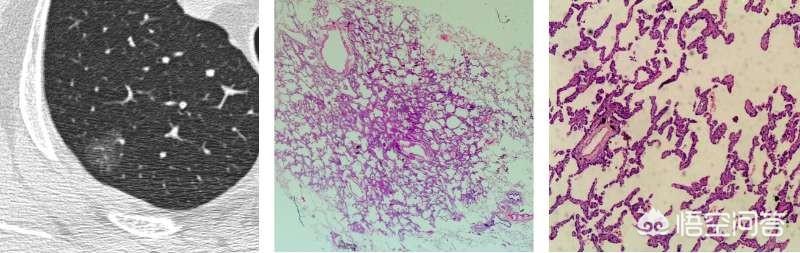

通常、異型腺腫性過形成の病変は5mm以内で、8mmを超えることは比較的まれである。下は8mm大の異型腺腫様過形成のCTと病理像である。

手術の機会に達していないと思われる、あるいは非定型腺腫様過形成の段階にある可能性のある地肌結節の場合。経過観察中に、すぐに手術が必要な状態とは??フィルム読者は、病変の前後を注意深く比較し、もし病変が見つかったら病変が以前の病変よりわずかに大きいか、あるいはわずかに密度が高いか、あるいは血管が病変の中に伸びているのが見つかる。例えば、下の写真は手術の時期だ。